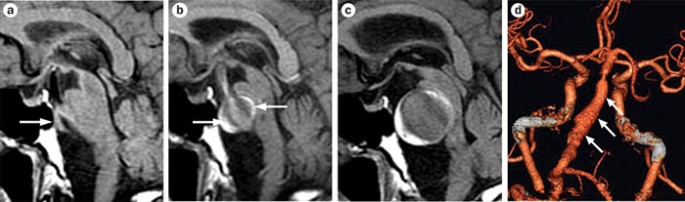

Intracranial Aneurysms From Vessel Wall Pathology To Therapeutic Approach Nature Reviews Neurology